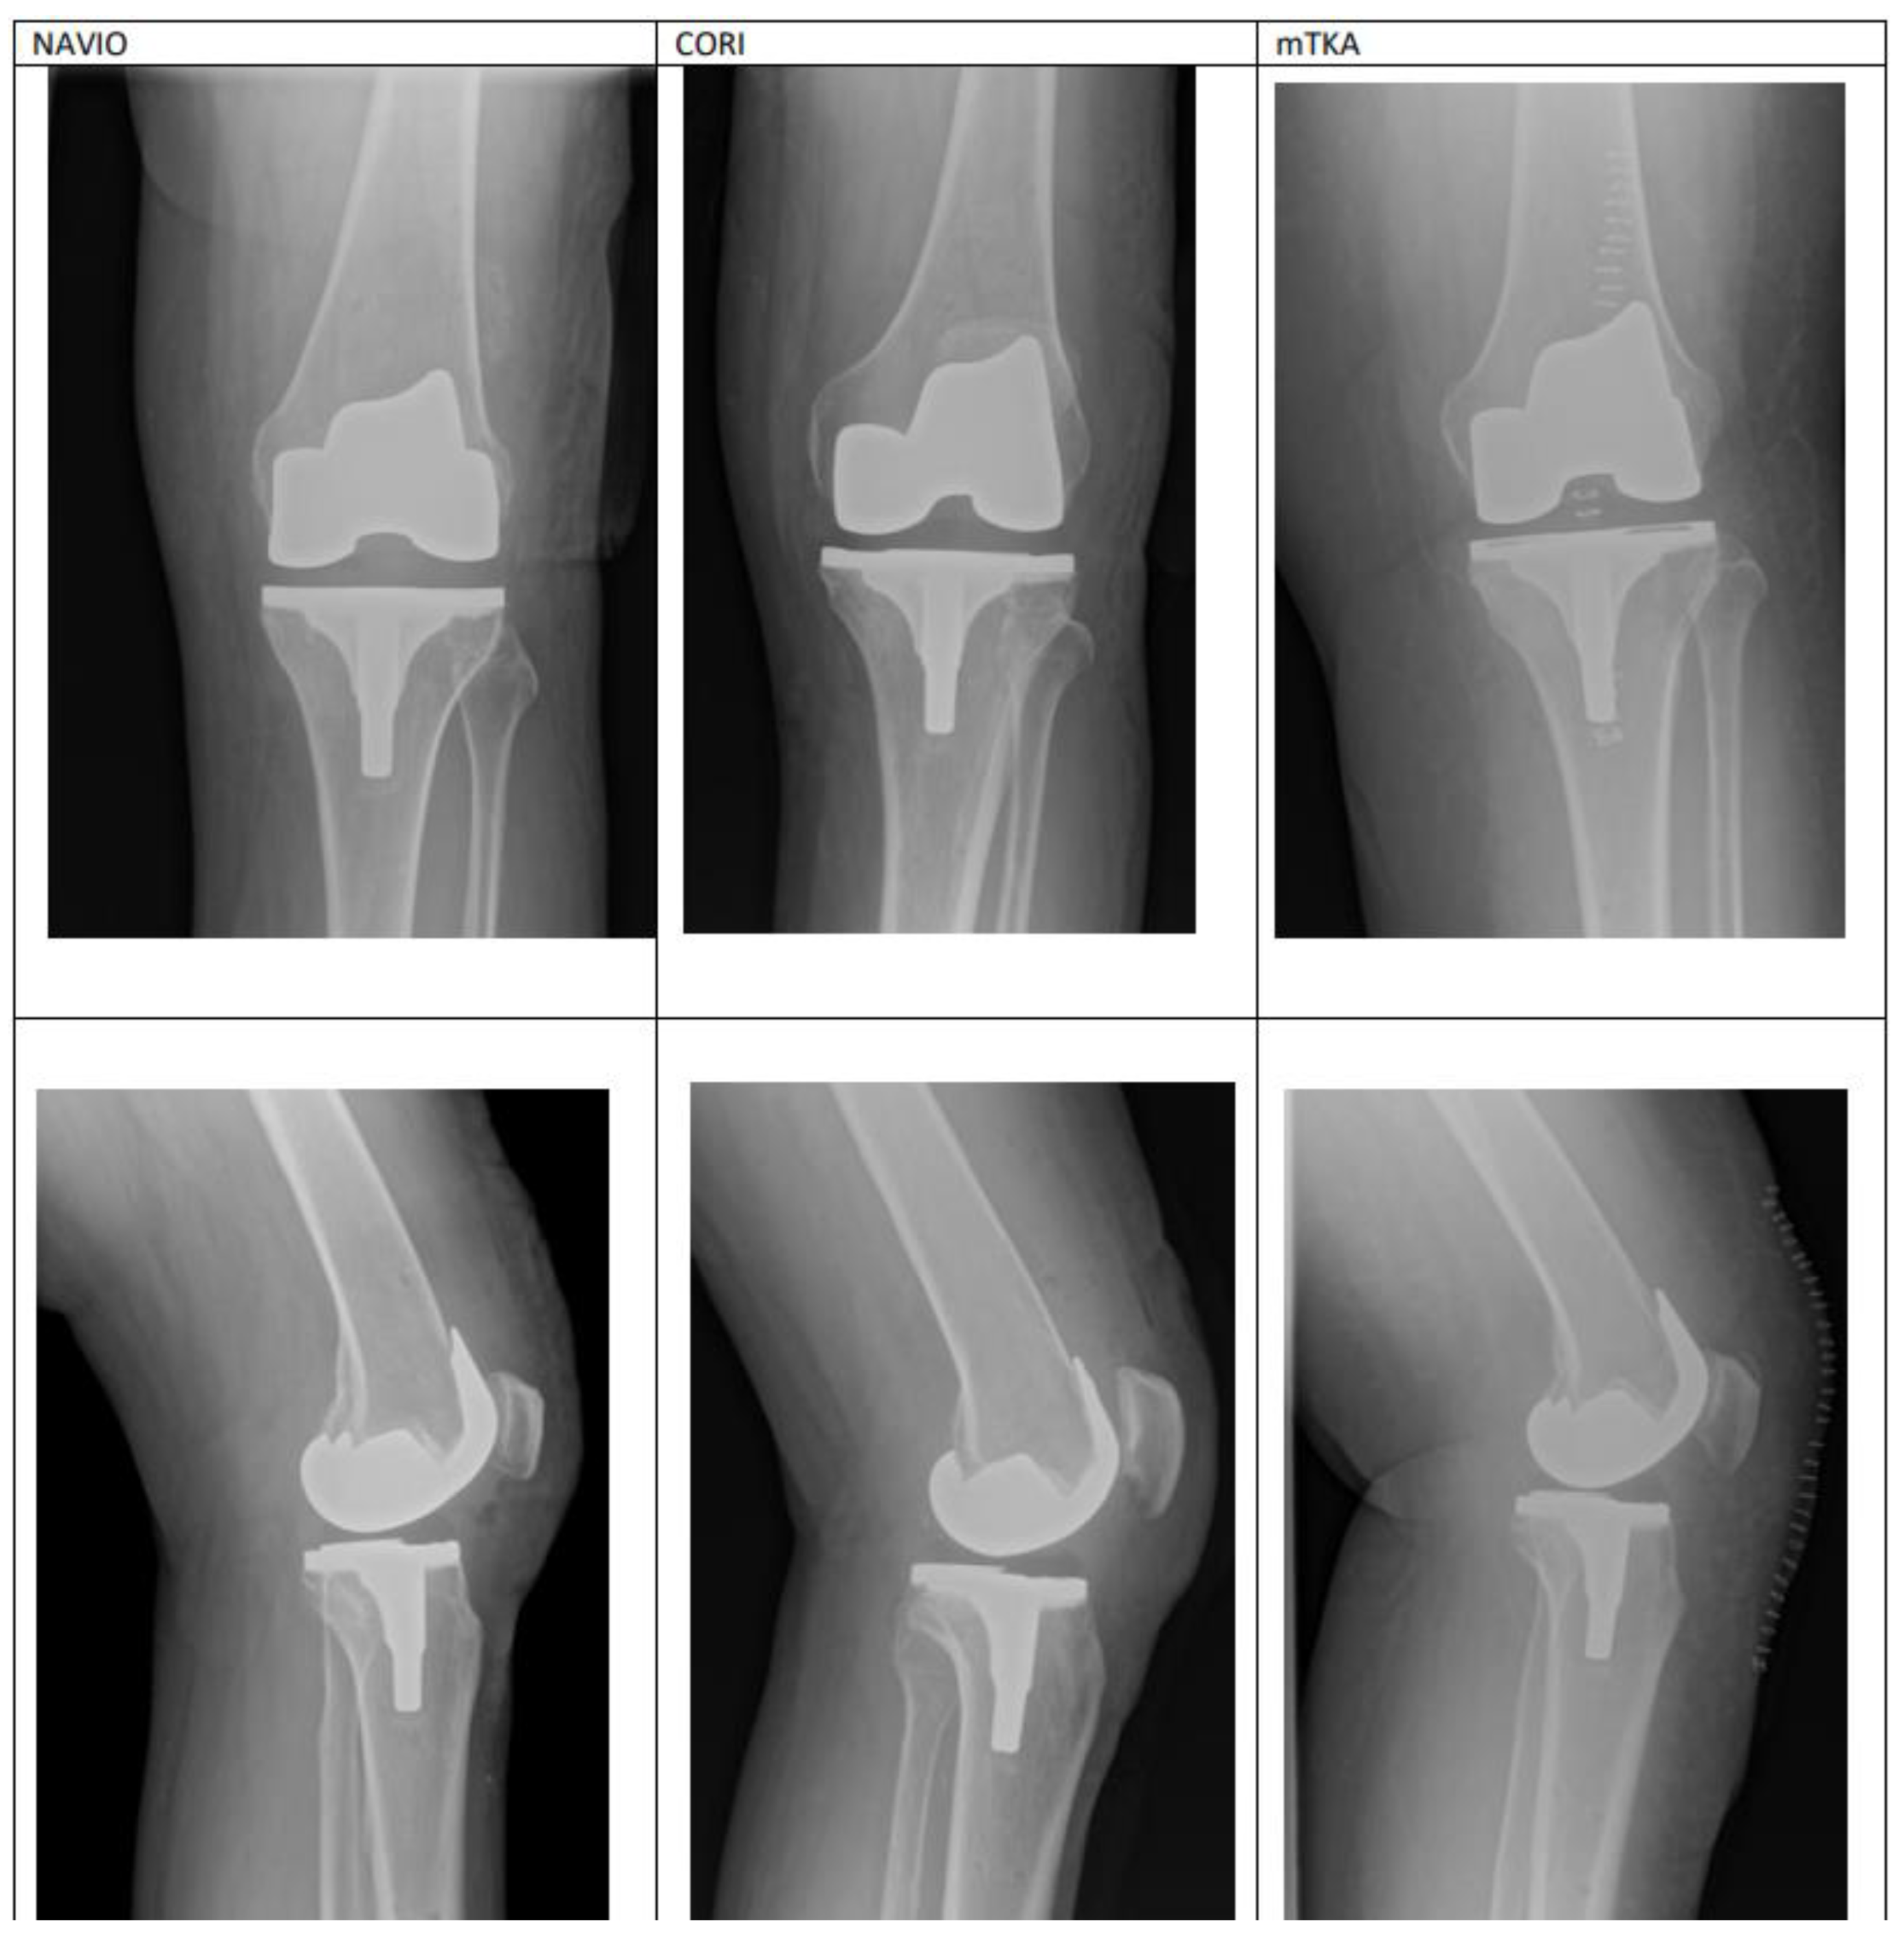

3.4. Complications

There were no between-group differences in terms of the frequency with which complications occurred. Neither group had delayed complications, such as: Infection, patellar dislocation, patellar fracture, supracondylar fracture, peroneal nerve palsy, periprosthetic fracture, thromboembolism, compromised wound healing occurred and no robotic-specific complications such as: Pin site fracture or pin tract infection occured, and no revisions were reported in either group. No deep infection occurred in these knees. No complications were detected on contol X-rays. Figure 4 presents the example of X-ray imaging performed on patients from each group during hospital stay (Table 1).

Figure 4.

Control entitled X-rays from the day following each procedure: NAVIO and CORI ra-TKA, and mTKA.